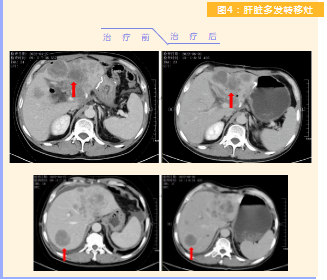

患者完成1周期治療后,上腹部疼痛癥狀基本消失,梗阻性黃疸癥狀緩解,腫瘤指標(biāo)下降(圖1),肺部多發(fā)轉(zhuǎn)移灶消失和縮小(圖2),雙肺門淋巴結(jié)縮?。▓D3),肝臟多發(fā)轉(zhuǎn)移灶縮?。▓D4)。